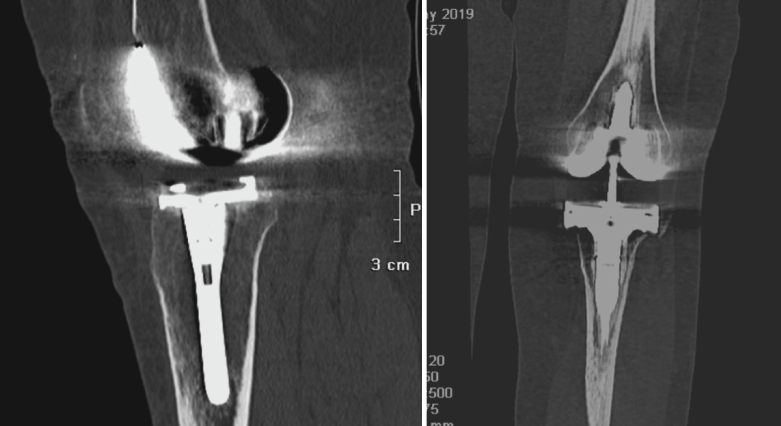

4. Prótesis (Figura 27)

Figura 27. Corte de reconstrucción sagital y coronal de tomografía axial computarizada de rodilla: se valoran los componentes femoral y tibial de la prótesis total.